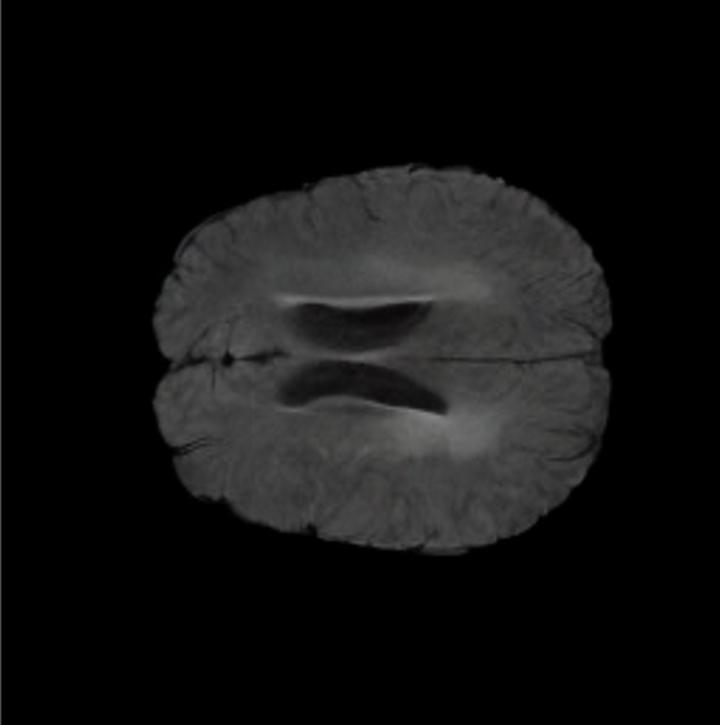

Our results unequivocally highlight the superior performance of X-Diffusion in terms of both qualitative and quantitative metrics. Representative MRI volumes generated by our pipeline, when juxtaposed with ground-truth images, showcased remarkable similarity, with even intricate physiological features like tumor information, spine curvature, and fat distribution being accurately captured.

Notably, X-Diffusion achieves sota dB for a few input slices while baselines require more than 60 input slices to achieve similar performance (Figure 7). The margin is more than 12 dB PSNR for the 1-slice input in both the BRATS and the UK Biobank benchmarks (see Table 1 and Figure 6). For reference, two randomly sampled MRIs from the UK Biobank would have a PSNR of 15.95 dB 0.36 (on 4800 randomly sampled examples). The slices from 3D reconstructed volumes at varying depths and axis of rotation visually match the ground truths (see Figures 5 and Figure 4). We also plot the error map (Figure 4) of such X-Diffusion generations to highlight the differences with the ground truth MRIs.